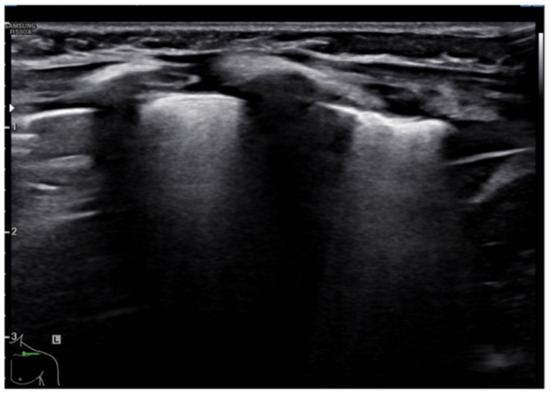

Transient tachypnea of the newborn (TTN), also known as “wet lung,” is caused by a failure in the reabsorption of fluid from the fetal lung. It is typical of term or post-term infants in the case of rapid delivery or cesarean section [24]. Infants with TTN present compact B-lines in the lower lung fields and fewer and less compact B-lines in the upper fields in one or both lungs. These signs, also known as double-lung points, appear because of the greater involvement of the lower lung fields in the disease and are characterized by a sharp ultrasound demarcation line between the upper and lower lung fields of both lungs (Figure 5) [17]. The pleural line is regular, with normal echogenicity and movement with respiratory acts. In contrast to NRDS, no subpleural consolidations are observed. Due to these typical ultrasonographic findings, much evidence has shown how pulmonary ultrasonography can be useful in the early diagnosis of TTN and differentiate TTN from NRDS already by the first hours of life [25].

Transient tachypnea of the newborn. The dashed line shows the ultrasound demarcation line between the upper and lower lung fields: double-lung point (white arrow).